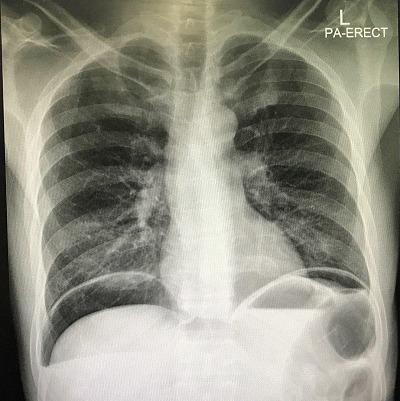

This case has interesting images of huge hydro pneumoperitoneum. It is a rare view in the medical practice and a good point to learn one of the complications of perforated duodenal ulcer and failure of omental patch operation. We reported a case of acute abdominal pain with hydro pneumoperitoneum that appeared as an air fluid line in X-ray. The patient had an omental patch surgery. Two days after the operation he got severe abdominal pain. The X-ray images showed significant huge hydro pneumoperitoneum. He underwent urgent surgical intervention for exploration that detected a large amount of gases, a biliary free fluid and a leak from duodenal ulcer. Omental buttressing was then performed.

该病例有巨大气腹积气的有趣影像。这在医学实践中是一种罕见的情况,也是了解十二指肠溃疡穿孔和网膜修补手术失败的并发症之一的好机会。我们报告了一例急性腹痛伴气腹积气的病例,X线显示为气液平面。该患者接受了网膜修补手术。术后两天,他出现剧烈腹痛。X线影像显示有明显的巨大气腹积气。他接受了紧急手术探查,发现大量气体、无胆汁的液体以及十二指肠溃疡渗漏。随后进行了网膜支撑术。